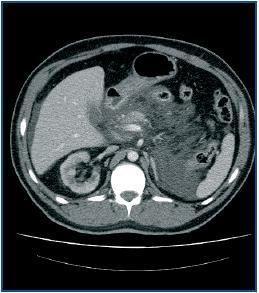

Two months following the removal of the catheter, and due to preference for this technique, peritoneal dialysis was restarted. Two days later, the patient was seen again with a clinical picture similar to acute pancreatitis, confirmed by cell count of leukocytes of 153 (26% PMN), amylase 418.

Abdominal CAT showed moderate acute pancreatitis. On admission, treatment with antibiotics, digestive rest and fluid therapy was started.